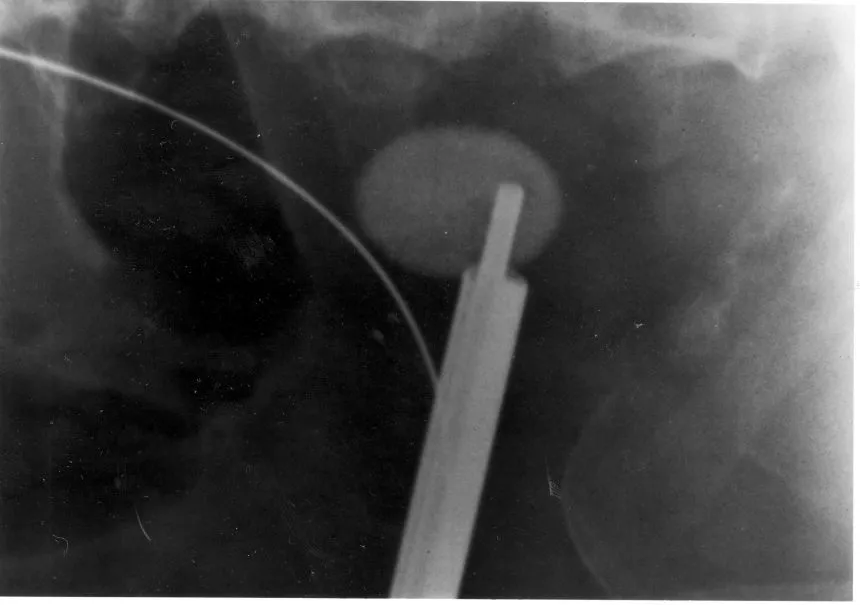

Vesekő Vesekő Nagyméretű vesekő és a hozzá vezetett ultrahangos zúzóeszköz röntgenfelvételen. Kategória Diagnosztika Közzétéve: 2016. 04. 23. 14:55